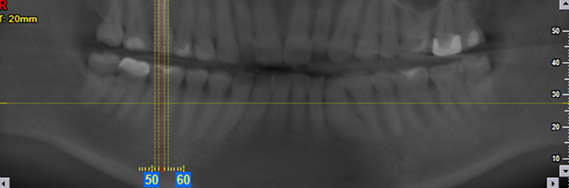

Digitale Panorama-Übersichtsaufnahme des Gebisses zur Befundung durch den Zahnarzt.

• Panoramaschichtaufnahme (OPG): Dieses Bild gibt uns einen vollständigen Überblick über Ihren gesamten Kiefer. Es zeigt uns den Platzbedarf für Implantate und wichtige Strukturen wie Nervenbahnen oder Kieferhöhlen.